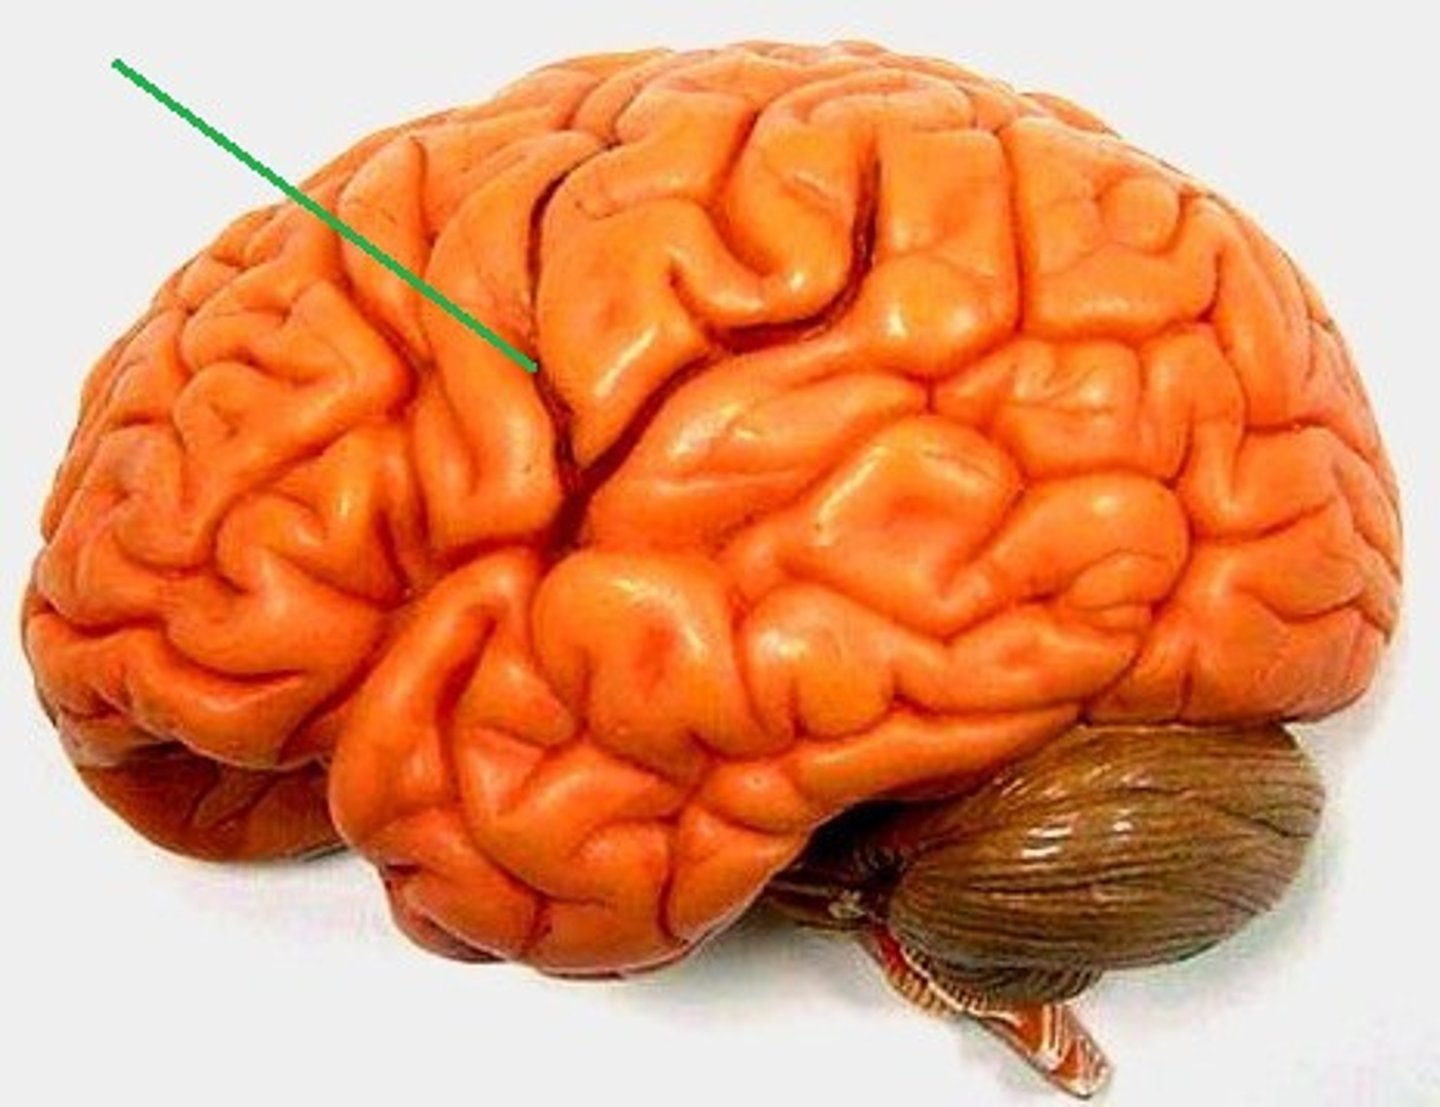

central sulcus

lateral sulcus

precentral gyrus

postcentral gyrus

frontal lobe

temporal lobe

parietal lobe

occipital lobe

Broca's area

Prefrontal cortex

Premotor cortex

Wernicke's area